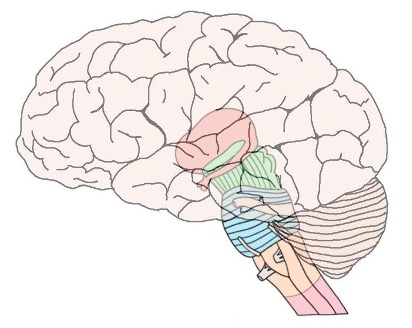

Have you or your child experienced symptoms like digestive issues, anxiety, breathing difficulties, heart palpitations, or frequent illness—and wondered if there’s a common thread? One potential root cause lies within the nervous system, in a structure called the vagus nerve. What Is the Vagus Nerve? The vagus nerve (cranial nerve X) is the longest and…